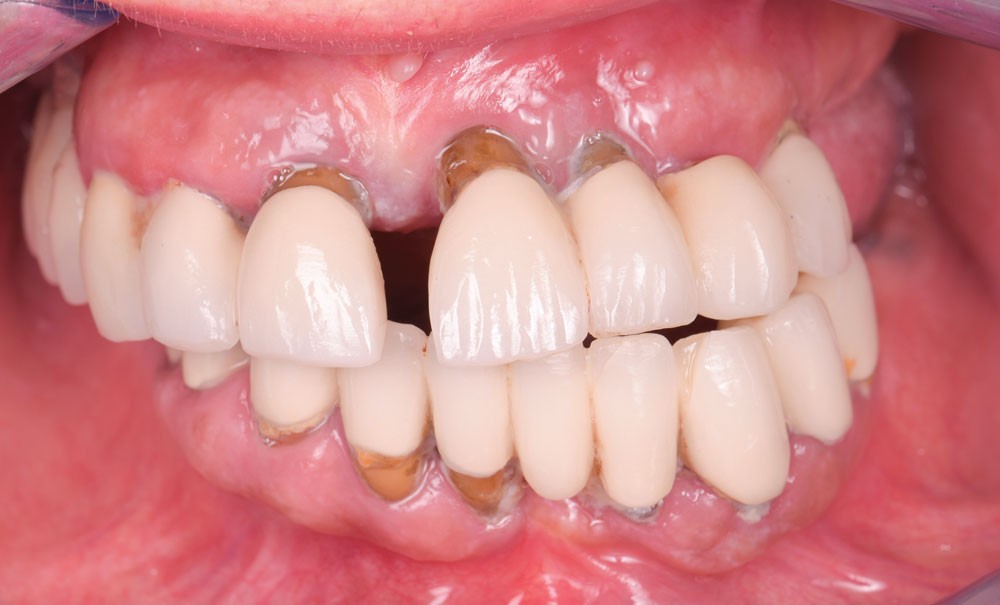

La présence de grande mobilité dentaire, associée à une latérognathie squelettique mandibulaire importante a occasionné ici un désordre esthétique et fonctionnel considérable (fig. 1a-b).

Les examens cliniques et radiographiques permettent de diagnostiquer de nombreuses reprises de caries sous les prothèses existantes, une parodontite chronique terminale, associée à de nombreuses migrations dentaires, posant l’indication de l’avulsion de l’ensemble des dents maxillaires (fig. 2).